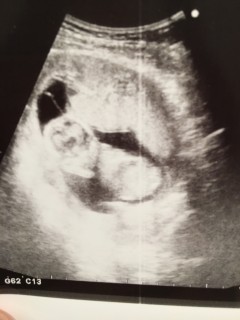

1ヶ月ぶりの検診でした! 寝ているのか動かなかったけど心臓は元気に動いてました♡ はっきり赤ちゃんの形しててかわいかったなぁ♡ 早く会いたい(*^^*)

今日も、順調で、安心しました。 性別が分かると良かったんですが、エコーの間、正面を向いて、ちょこんと座り動いてくれず…。 ちょっと角度を変えて、横向きに撮れたところです。 1ヶ月後、また、元気な様子が見れますように。

14週の妊婦検診にて。 主人は初めて一緒に経腹エコー見ました。ベビちゃん朝は爆睡。しっかり寝て動きもしなかったです。心臓はしっかり動いてますと先生に言われ、ほっと一安心しました。 下を向いて腕を支えにして、爆睡しているのが可愛いです。 次は動いているところが見れるといいなー!